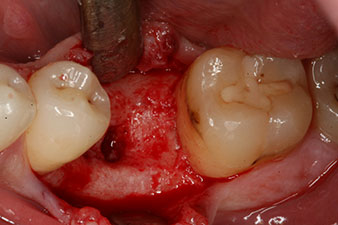

Le couple utilisé pour la pose guidée était de 43 Ncm.

En outre, après avoir vissé une tige de mesure (SmartPeg) spécialement conçue pour l'implant, la valeur ISQ a été mesurée à l’aide de la sonde du module W&H Osstell ISQ.

Ce module est fourni en option avec l’Implantmed de W&H et est fixé au moteur d’implantologie (cf. Fig. 11). La valeur ISQ adimensionnelle mesurée immédiatement après l’insertion était de 64 dans l’axe oro-vestibulaire et de 68 dans l’axe mésio-distal (valeur maximale = 100).

Ces valeurs auraient pu indiquer une cicatrisation ouverte, voire une restauration immédiate. Étant donné le volume osseux crestal insuffisant au niveau de l’implant, une augmentation osseuse a été pratiquée localement à l’aide des fragments osseux recueillis lors de la préparation du lit implantaire, et des points de suture effectués pour éviter le contact de la salive.